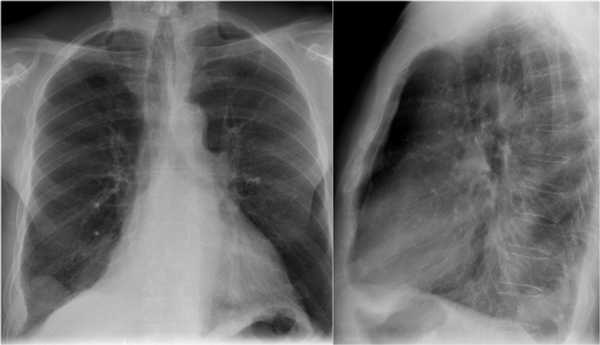

На рентгенограмме представлен тотальный коллапс верхней доли левого легкого. Обратите внимание на высокое стояние левого корня легкого. Спавшаяся верхняя доля левого легкого расположено позади грудины. В данном случае компенсаторная гипервентиляция нижней доли левого легкого повлияло на то, что позиция диафрагмы и средостения в норме.